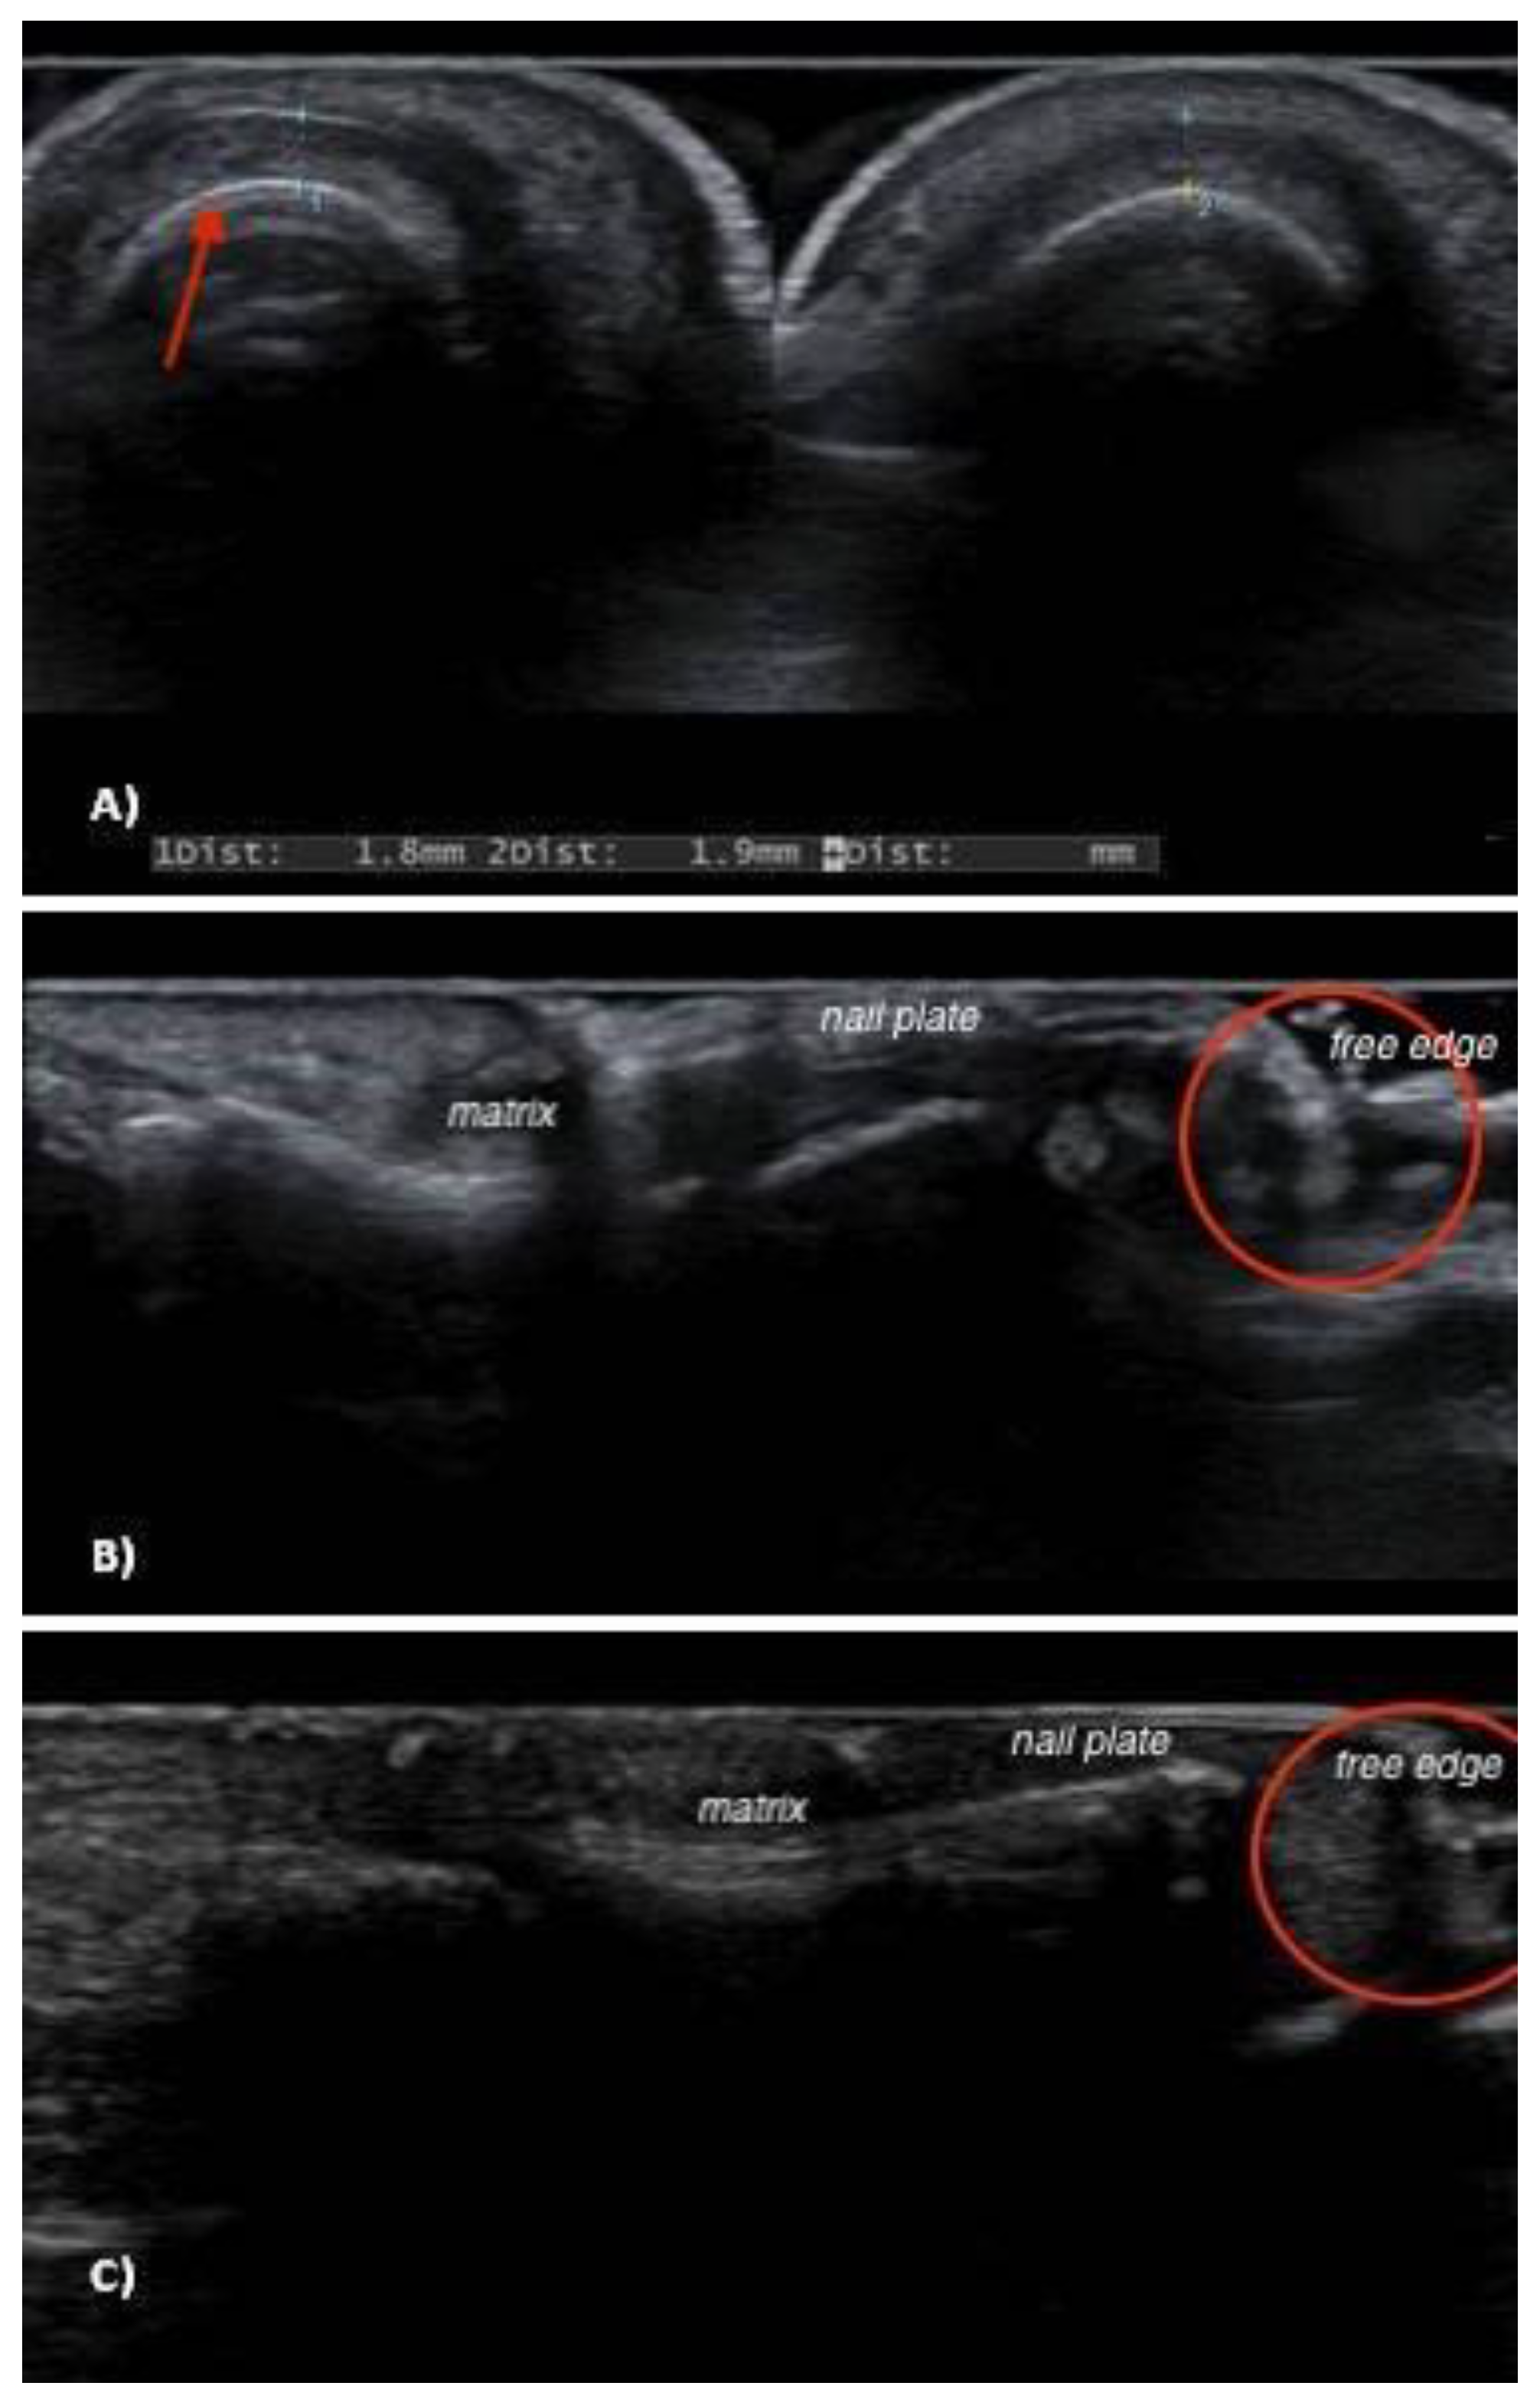

| Patient (Age, Sex) | Clinical Features | Ultrasonography | ||

|---|---|---|---|---|

| Nail Bed Dishomogeneity | Distal Subungual Mass | Doppler Signal | ||

| 1 (M, 66) | Melanonychia | NO | YES, hyperechoic | NO |

| 2 (M, 71) | Erythronychia | NO | NO | NO |

| 3 (F, 64) | Melanonychia | YES | YES, hyperechoic | NO |

| 4 (F, 34) | Erythronychia | YES | YES, hyperechoic | NO |

| 5 (F, 23) | Splinter hemorrhages | YES | YES, hyperechoic | NO |

| 6 (F, 75) | Erythronychia | NO | YES, hyperechoic | NO |